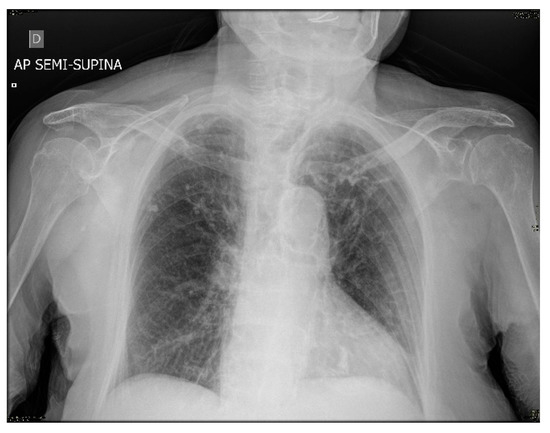

Since at the time of the hospital admission, in Italy, the COVID-19 pandemic was still in its infancy and the molecular swabs for SARS-CoV-2 were not available in Viterbo. The hospital health care providers did not deem it appropriate to send the patient to a hospital of a different city for the molecular swab. However, later on, a lung specialist released a medical report based on the hospital medical records, showing an image compatible with SARS-CoV-2 infection, as suggested by chest X-ray results (Figure 1).

Figure 1.

Anterior chest X-ray of the centenarian patient showed a thickening of the peribronchial and bronchilovascular interstitium, probably due to interstitial disease.

The clinical case here described regards a centenarian woman without previous medical illness and disability, who was very likely infected with SARS-CoV-2 in late February 2020, as strongly suggested by the symptoms presented at her hospital admittance and by the later report released by a respiratory specialist confirming a condition compatible with COVID-19 pneumonia (Figure 1). Regardless of her very advanced age, the patient recovered well from COVID-19 and her anti-virus antibody response was taken into account. Specifically, IgG antibodies directed against SARS-CoV-2 spike S1 were evaluated twice and up to 1 year after the symptoms’ onset. The measurement of circulating specific antibodies was paralleled by the evaluation of specific antibodies released in vitro by memory B cells (Figure 2). The main finding of this report is that while the serological analyses performed more than 4 months up to 1 year after infection were negative, the Cell-ELISA data were positive and fairly constant over time, suggesting a long lasting immune memory linked to B lymphocytes. This finding was confirmed when the values obtained from the centenarian patient’s samples were compared with samples from control aged subjects, either negative or positive for virus swab and for both serology and cell-ELISA (Figure 2), highlighting that the observed memory response in the patient is in line with a previous SARS-CoV-2 infection.